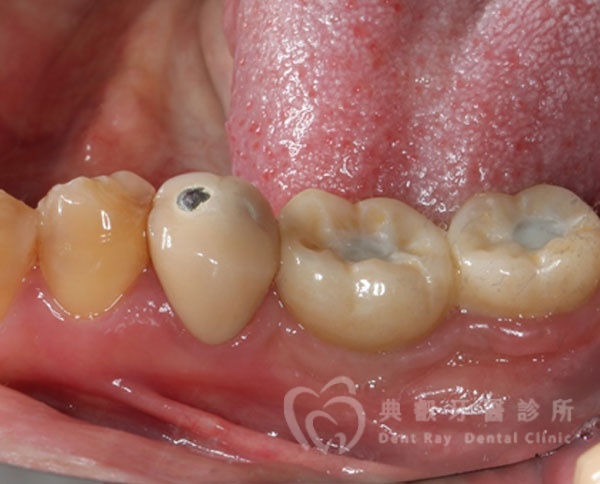

植牙案例三